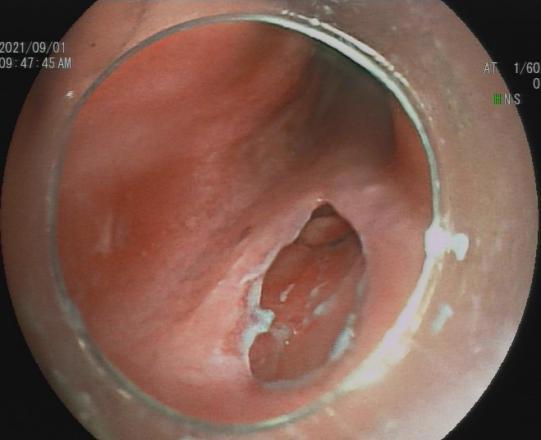

三、早期消化道肿瘤ESD技术

内镜下粘膜剥离术(ESD),具有超级微创、安全性高、住院时间短及费用低等优势。

直肠巨大绒毛状腺瘤 内镜下粘膜剥离过程

粘膜剥离术后创面 剥离的巨大腺瘤